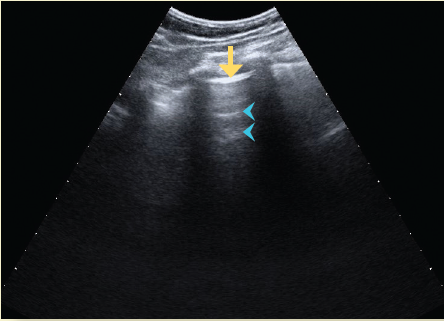

El ultrasonido es un método seguro, transportable a la cama del paciente, libre de radiación ionizante y de bajo costo, por lo que es útil en el diagnóstico y monitoreo de pacientes con infección por SARS-CoV-218. El hallazgo principal en ultrasonido es la enfermedad intersticial aguda, que produce artefactos hiperecoicos verticales que se apartan de la línea pleural, llamadas líneas B. El pulmón que pierde su contenido aéreo progresa de presentar un patrón pulmonar normal (con líneas A, las cuales se caracterizan por ser horizontales, cortas e hiperecoicas) a observar líneas B no coalescentes, después líneas B coalescentes hasta llegar a la consolidación19-21 (figuras 5a, 5b, 5c, 5d).

Figura 5a Ultrasonido en escala de grises del tórax donde se observa la línea pleural (flecha amarilla) y las líneas A (cabezas de flecha), que corresponden al patrón pulmonar ecográfico normal